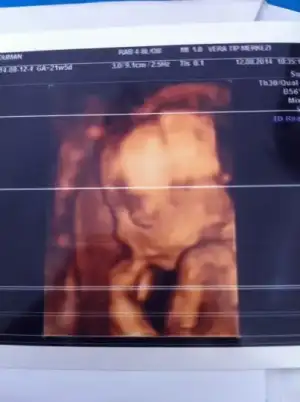

Kızlarrr veeeeee ikînci kez bebişimi renklı gordum.

Eklentiler

• image.webp

image.webp

9 KB · Görüntüleme: 76

ben 20+6da gittiğimde renkliye verdi ama tam gözükmedi daha büyümesi lazım dedi doktorum...bir daha gelince daha güzel gözükecek demişti...maşallah senin meleğine tam poz vermiş ya yerimm:KK48:..sorayım bir dedim acaba kaç haftalıktan tam gözüküyor diye...kendi doktorun renkliye verdi değil mi canım??